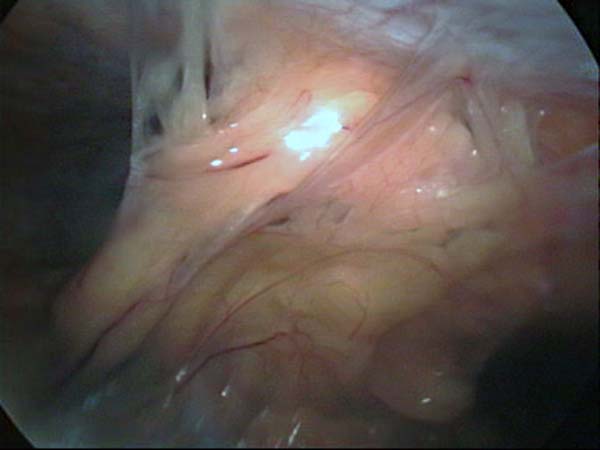

Laparoscopy Photos Ovarian Cyst Ovarian Cystectomy Uterine Septum Tubal Pregnancy